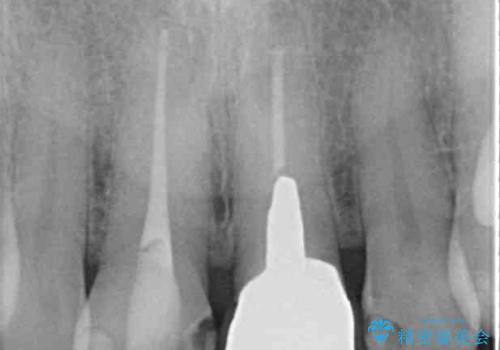

- 変色した保険の前歯のクラウンを交換したいとのことで来院された患者様です。

中心左側の歯はクラウンが装着されており、右側は神経組織が除去されて多少変色している状態でした。

右側の歯も将来的にもっと変色する可能性があるため、前歯2本をオールセラミッククラウンにて補綴治療を行うこととしました。